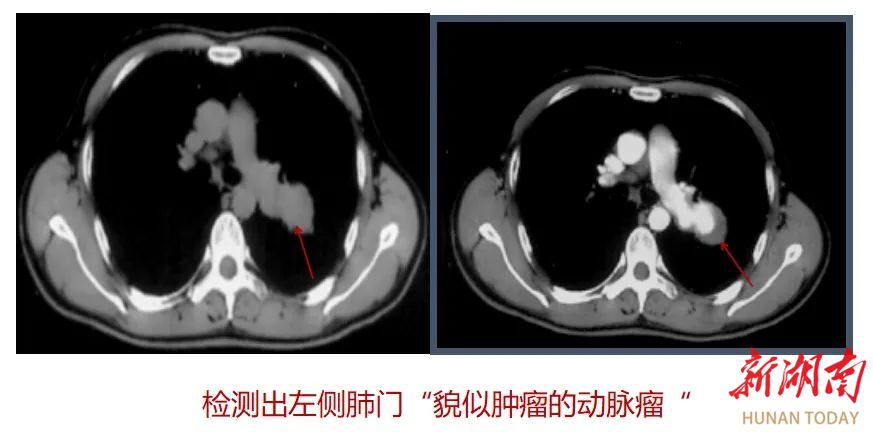

三、检出血管病变

3、检出并鉴别血管内病变